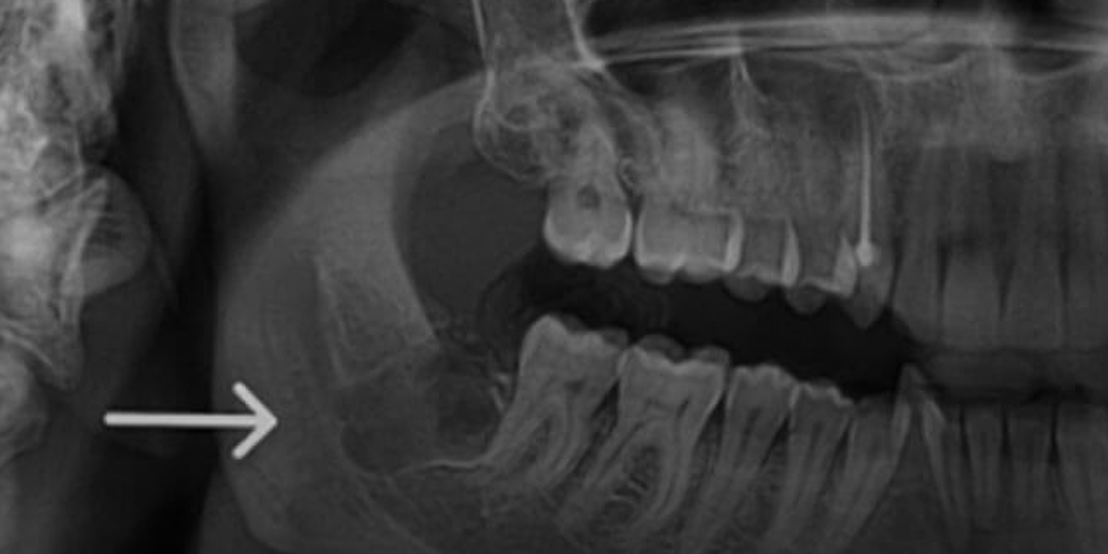

Surgical Extraction

As part of the best wisdom tooth extraction Dubai options, it ensures optimal care, comfort, and long-term oral health.